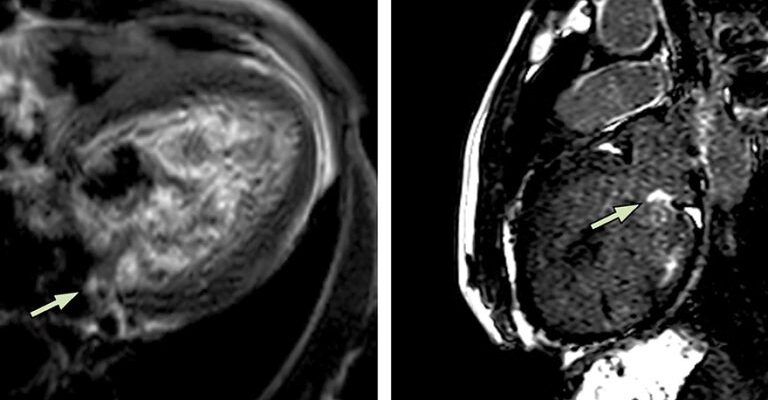

Kardiyak MR, çeşitli kalp hastalıklarının tanısında ve takibinde kullanılır. Özellikle kalp kası hastalıkları (kardiyomiyopatiler), doğumsal kalp hastalıkları, kalp kapakçık hastalıkları, koroner arter hastalıkları ve perikardit gibi durumlarda çekilir. Ayrıca, kalp tümörlerinin ve kalp içindeki pıhtıların tespitinde de kullanılabilir.

Kardiyak MR ile teşhis edilebilen hastalıklar arasında kardiyomiyopatiler, doğumsal kalp hastalıkları, kalp kapakçık hastalıkları, koroner arter hastalıkları ve perikardit gibi hastalıklar bulunur. Ayrıca, kalp tümörleri ve kalp içi pıhtılar da bu yöntemle tespit edilebilir.